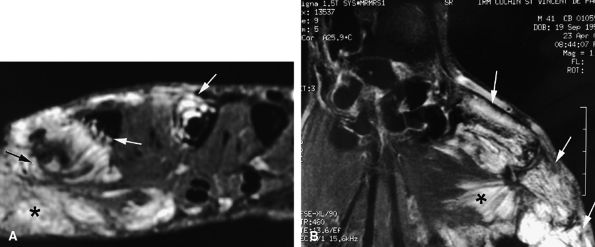

FIGURE 11.134 ● Postoperative recurrence of glomus tumor. Axial T1-weighted images before (A) and after (B) injection of gadolinium and (C) MR angiogram. Artifacts from the previous lateral surgical approach (arrows) can be seen, and there is tumor recurrence in the lateral part of the nail bed (asterisk). The lateral margins are blurred by scar tissue (arrowheads). On the MR angiogram, two contiguous tumors (arrows) can be seen. The proximal lesion displays ill-defined borders.

|

![]() |

FIGURE 11.135 ● Multiple glomus tumors. (A) MR angiogram depicting five glomus tumors in the same fingertip (arrows). (B) MR angiogram in a separate case shows glomus tumors of the fingertips of two adjacent fingers (arrows).